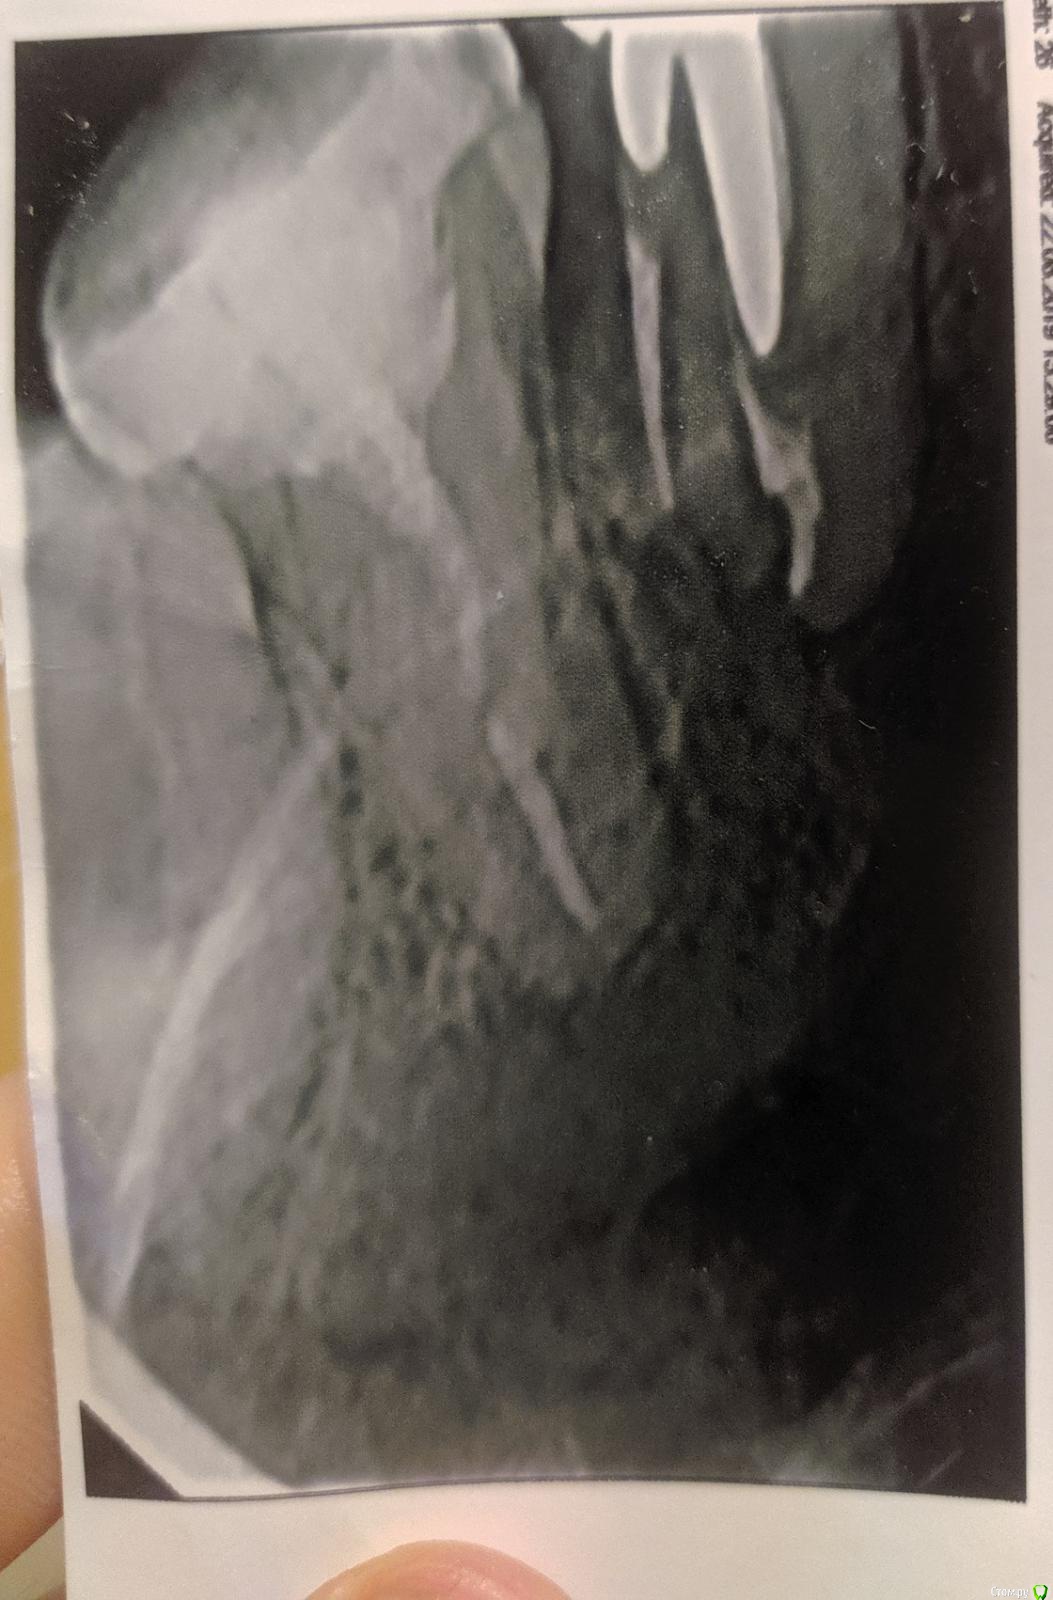

klemento Опубликовано 22 октября, 2019 Автор Поделиться Опубликовано 22 октября, 2019 Вы неправильно интерпритируете томограмму. Если вы утверждаете что клык явно чувствует золод, то проблем не должно быть просто лечите кариес в нем.Ну я просто увидел то пятнышко и подумал, что что-то не так.У меня последняя просьба к вам. Посмотрите пожалуйста если не затруднит 4 зуб снизу справа. Там есть перфорация? Лечил полгода назад, врач утверждал, что нашел и запломбировал второй канал. Он иногда побаливает. Если там всё же есть перелом или перфорация хочу обратиться к ним с претензией. Хотя прошло достаточно много времени и могут сослаться на что угодно... Ссылка на комментарий

krokomot Опубликовано 22 октября, 2019 Поделиться Опубликовано 22 октября, 2019 Ну я просто увидел то пятнышко и подумал, что что-то не так.У меня последняя просьба к вам. Посмотрите пожалуйста если не затруднит 4 зуб снизу справа. Там есть перфорация? Лечил полгода назад, врач утверждал, что нашел и запломбировал второй канал. Он иногда побаливает. Если там всё же есть перелом или перфорация хочу обратиться к ним с претензией. Хотя прошло достаточно много времени и могут сослаться на что угодно...зуб 4й с проблемой, потребуется его удаление, вам не повезло форма вашего корня не подходит для стандартного протокола лечения канала так как имеет значительную щелевидную вогнутость в виде запятой, зуб симметричный с другой стороны имеет такую же форму и если вы доведете зуб до лечения каналов скорее всего с ним будет тоже самое. Лечение каналов не подпадает под закон о защите прав потребителей....Вы должны были предоставить томограмму перед лечением каналов для большего успеха, но томограмма не входит в стандартный протокол лечения, а на обычных снимках корень будет выглядеть как обычный, а не как у вас.http://forum.stom.ru/topic/39173-vrach-ne-zametila-odin-kanal-v-zube-i-sootvetstve/ Ссылка на комментарий

klemento Опубликовано 23 октября, 2019 Автор Поделиться Опубликовано 23 октября, 2019 зуб 4й с проблемой, потребуется его удаление, вам не повезло форма вашего корня не подходит для стандартного протокола лечения канала так как имеет значительную щелевидную вогнутость в виде запятой, зуб симметричный с другой стороны имеет такую же форму и если вы доведете зуб до лечения каналов скорее всего с ним будет тоже самое. Лечение каналов не подпадает под закон о защите прав потребителей....Вы должны были предоставить томограмму перед лечением каналов для большего успеха, но томограмма не входит в стандартный протокол лечения, а на обычных снимках корень будет выглядеть как обычный, а не как у вас.http://forum.stom.ru/topic/39173-vrach-ne-zametila-odin-kanal-v-zube-i-sootvetstve/Печально конечно. Спасибо за ответы. Ссылка на комментарий